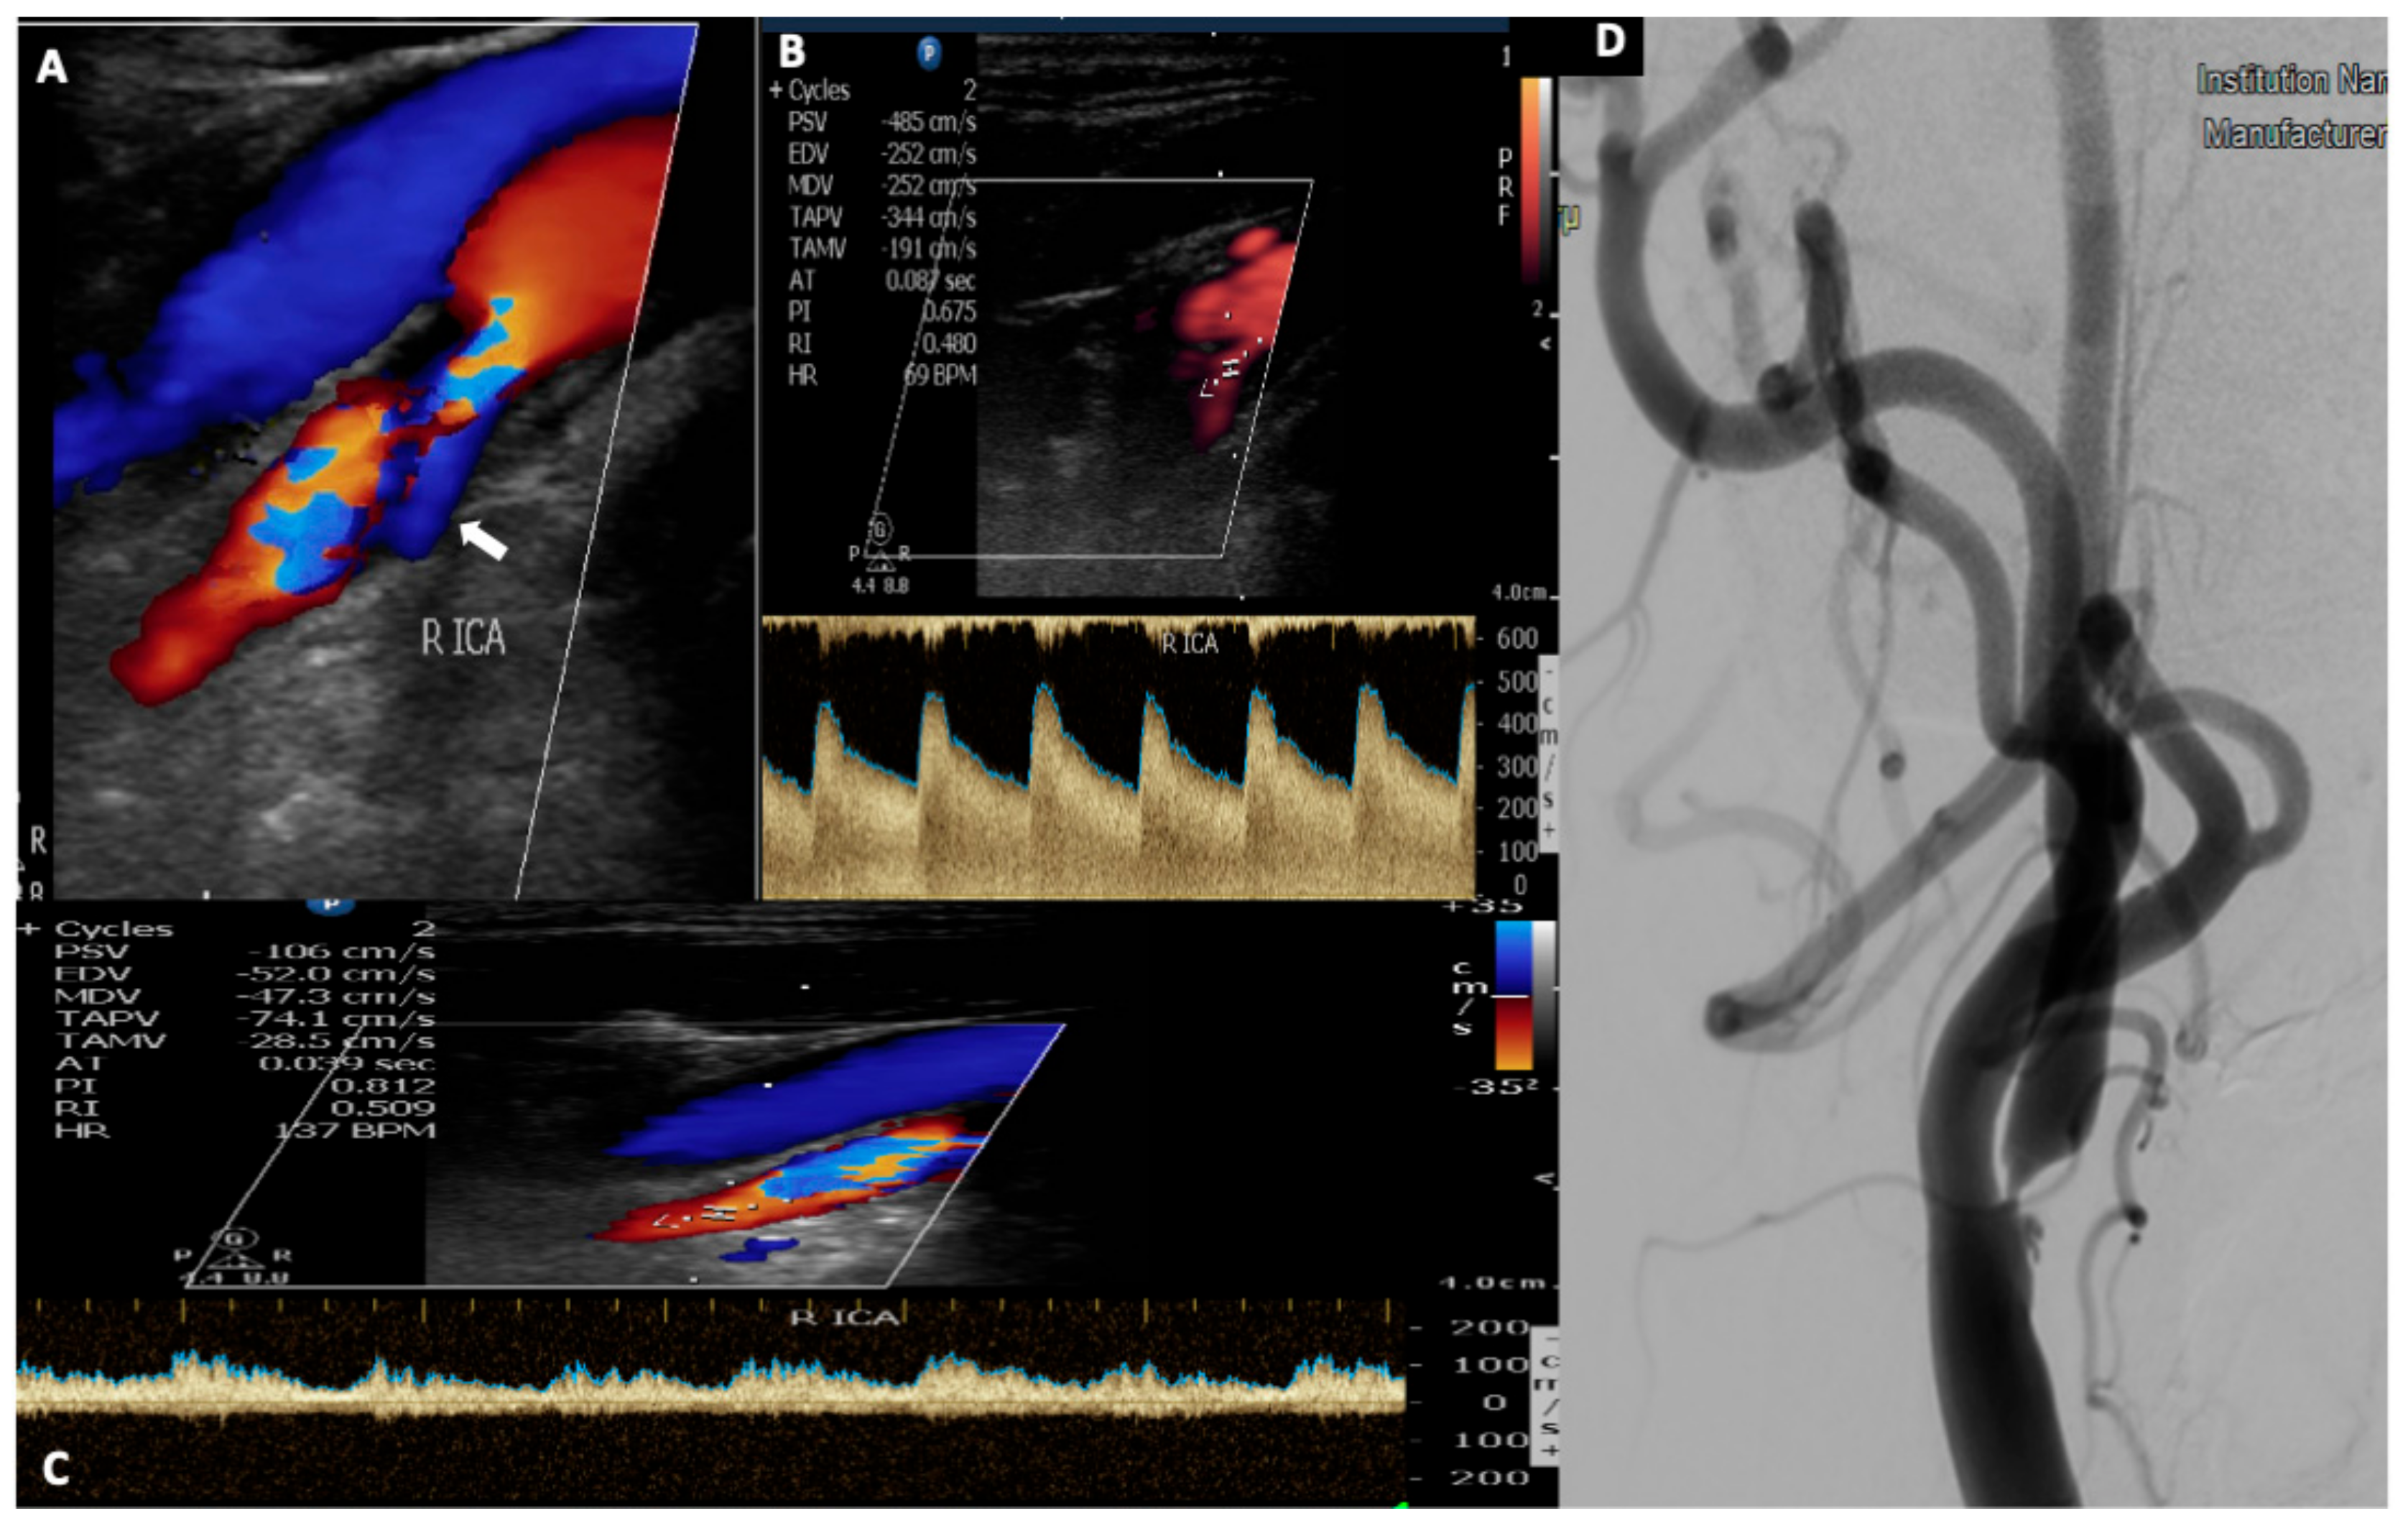

Medicina Free Full Text Ultrasound Assessment Of Extracranial Carotids And Vertebral Arteries In Acute Cerebral Ischemia Html